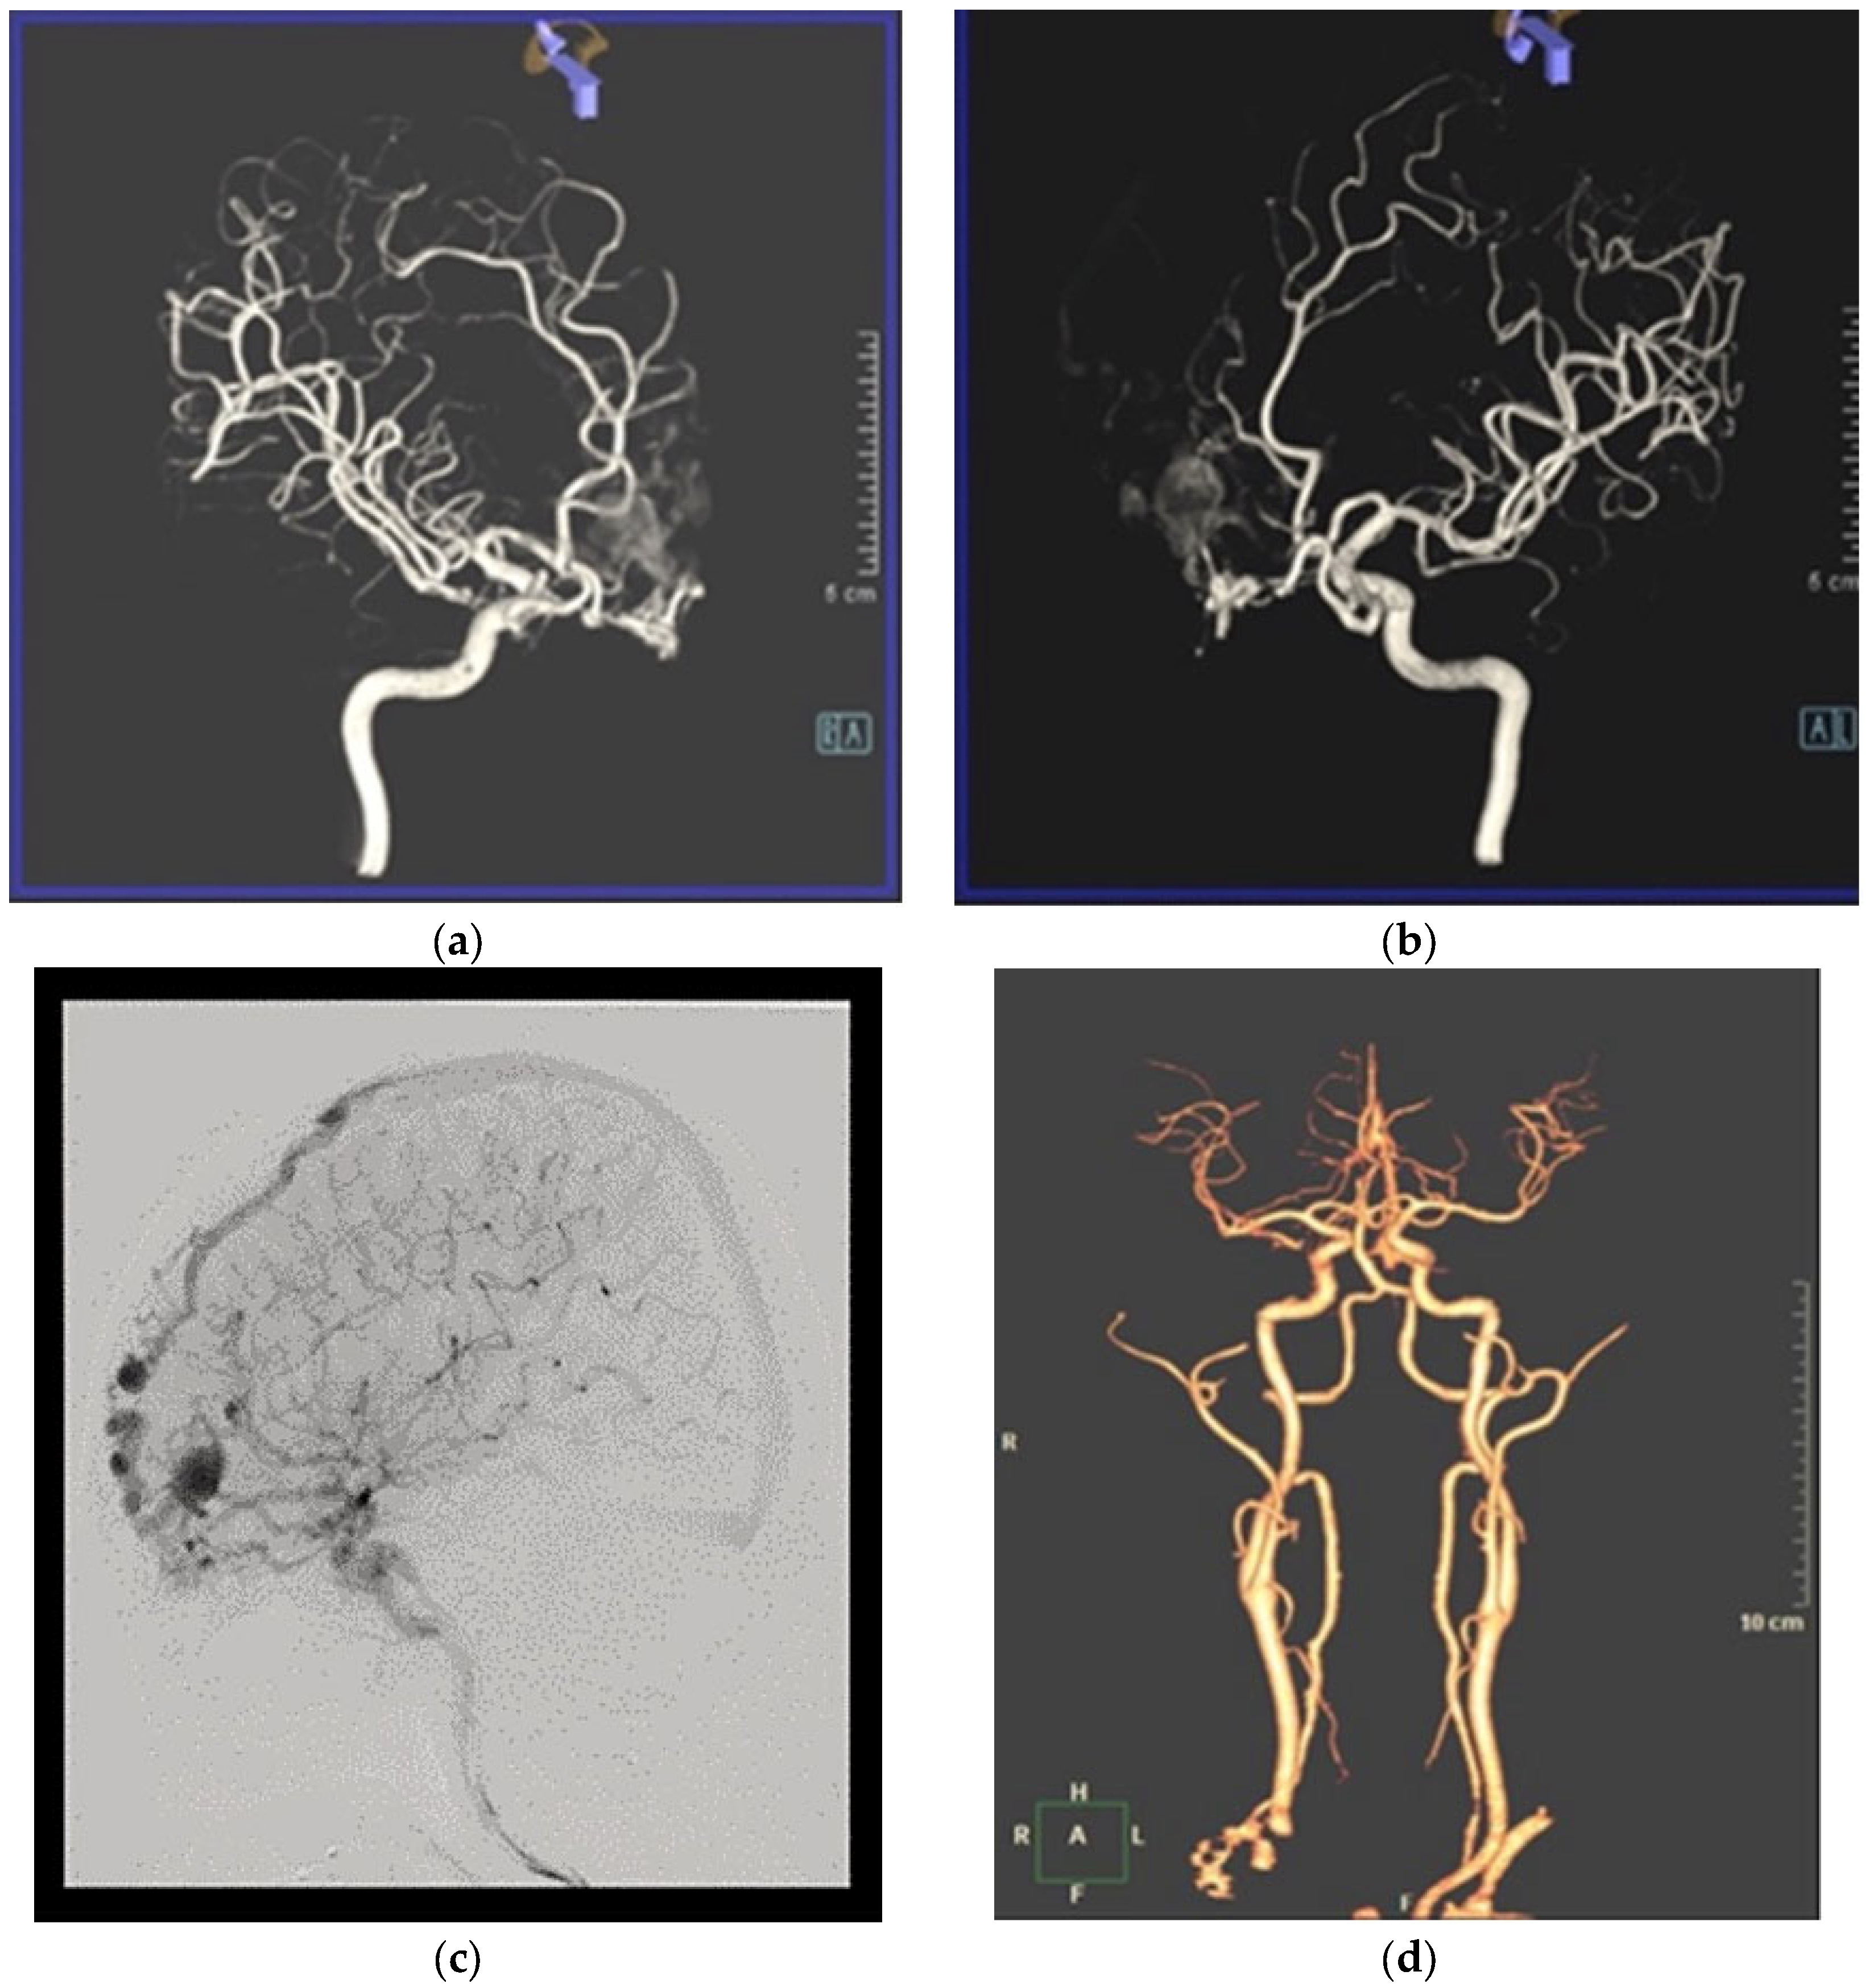

2. Case Report